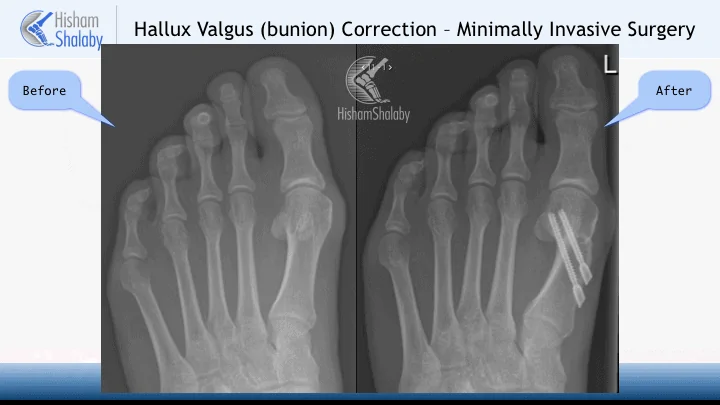

The operation involves two small incisions on the medial side of the big toe. One is used to shave the bunion with a special burr and to perform a cut in the bone with another burr. Through the same incision, the bone is displaced to correct the deformity.

Through the second incision screws are introduced to fix the translated bone. Further stab incisions may be needed to do a percutaneous Akin osteotomy.

The operation is done under x-ray guidance.

The gold standard surgical correction of the bunion deformity is the Scarf & Akin osteotomies. The minimally invasive technique is suitable for a group of patients where it can have the benefit of less scarring. The recovery period is the same following both techniques and there is no evidence in the current literature to suggest that this technique is better or worse than the open correction.